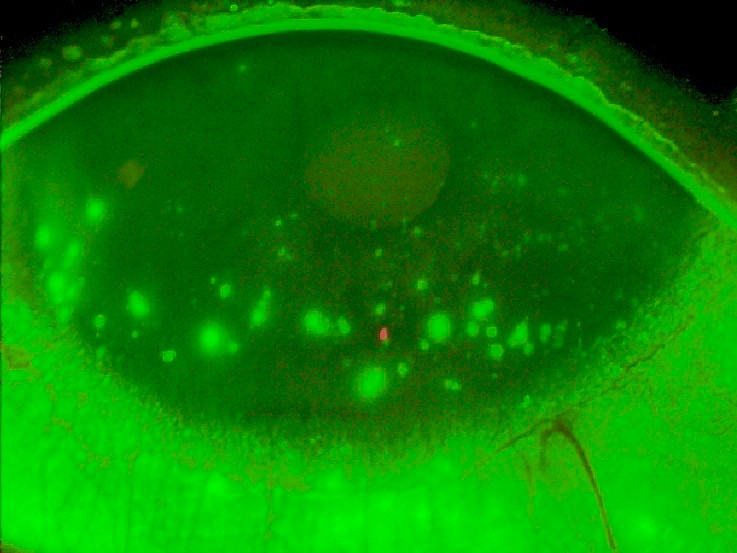

Optikere kan påvise tørre øyne med validerte spørreskjema og tradisjonelle tester som fluorescein break-up time (FBUT), vitalfarging med fluorescein og Schirmers test samt vurdering av meibumkvalitet og tømmingsgrad. Fluorescein break-up time benyttes for å studere tårefilmens stabilitet og predikerer tørre øyne dersom det påvises oppbrudd i tårefilmen innen ti sekunder etter siste blunk. Vitalfarging med fluorescein og inspeksjon i spaltelampe med blått lys og eventuelt gulfilter kan også avdekke inflammasjon ved tørre øyne ved at det påvises punktat fargeopptak («staining») av fluorescein i hornhinnen/bindehinnen (figur 2). Vurdering av meibumkvalitet og tømmingsgrad utføres ved å studere kvaliteten og mengden av fettstoffer fra de meibomske kjertlene for å avdekke meibomsk kjerteldysfunksjon (figur 3).